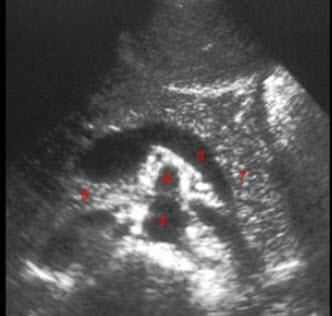

24、单项选择题

图示3所指部位()

A.脾静脉

B.腹主动脉

C.肠系膜上动脉

D.胰头

E.左肾静脉